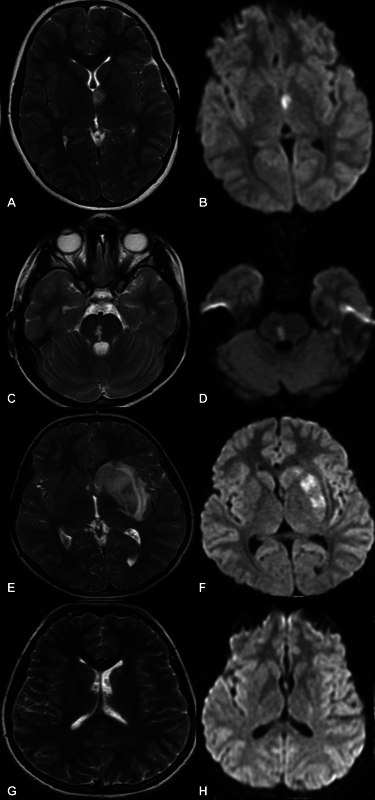

Abstract Image